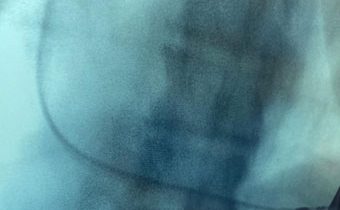

Caso Clínico: Marcapaso